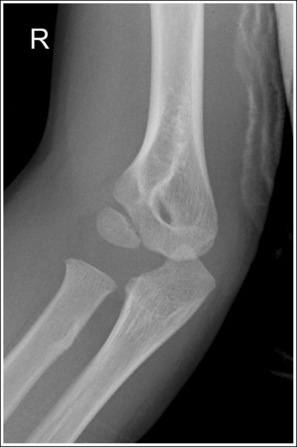

See Figure 4-76 and Box 4-20.

Contrast and density are adequate to demonstrate the anterior, posterior, and supinator fat pads, surrounding soft tissue, and bony structures.

• Fat pads on lateral elbow projection. To evaluate a lateral elbow projection, the reviewer not only analyzes the bony structure, but also studies the placement of the soft tissue fat pads. Three fat pads of interest are present on a lateral elbow projection, the anterior and posterior fat pads and the supinator fat stripe. The anterior fat pad should routinely be seen on all lateral elbow projections when adequate exposure factors are used. This pad is formed by the superimposed coronoid process and radial pads and is situated immediately anterior to the distal humerus (Figure 4-77). A change in the shape or placement of the anterior fat pad may indicate joint effusion and elbow injury. The posterior fat pad is normally obscured on a negative lateral elbow projection because of its location within the olecranon fossa. When an injury occurs, joint effusion pushes this pad out of the fossa, allowing it to be visualized proximal and posterior to the olecranon fossa. The supinator fat stripe is visible parallel to the anterior aspect of the proximal radius (see Figure 4-77). Displacement of this fat stripe is useful for diagnosing fractures of the radial head and neck.

The elbow is flexed 90 degrees.

• When the elbow is flexed 90 degrees, the forearm can be elevated to align the anatomic structures of the distal humerus properly, and displacement of the anterior and posterior fat pads can be used as signs to determine diagnosis. If the elbow is not adequately flexed, these fat pads can be displaced by poor positioning instead of joint pathology, interfering with their diagnostic usefulness. When the arm is extended, nonpathologic displacement of the anterior fat pad results from intraarticular pressure placed on the joint. Nonpathologic displacement of the posterior fat pad is a result of positioning of the olecranon within the olecranon fossa, which causes proximal and posterior displacement of the pad (see Image 87).

The elbow is in a lateral projection. The distal humerus demonstrates three concentric arcs, which are formed by the trochlear sulcus, capitulum, and medial trochlea. The elbow joint space is open, and the radial head is superimposed over the coronoid process.

• A lateral elbow projection is obtained when the humeral epicondyles are positioned directly on top of each other, placing an imaginary line drawn between them perpendicular to the IR. To obtain this humeral epicondyle positioning, place the humerus parallel with the IR and elevate the distal forearm until the palpable medial and lateral epicondyles are superimposed (Figure 4-78). This positioning aligns the trochlear sulcus, capitulum, and medial trochlea into three concentric (having the same center) arcs (Figure 4-79). The trochlear sulcus is the small center arc. It moves very little when a positional change is made and works like a pivoting point between the capitulum and medial aspect of the trochlea. The largest of the arcs is the medial aspect of the trochlea. It is demonstrated very close to and slightly superimposed on the curve of the trochlear notch. The intermediate-sized arc is the capitulum. When these three arcs are in accurate alignment, the elbow joint is visualized as an open space and the anterior and proximal surfaces of the radial head and coronoid process are aligned.

Figure 4-79 AP (left) and lateral (right) images showing anatomy of the distal humerus. (From Martensen K III: The elbow, In-Service Reviews in Radiologic Technology, 14[11], 1992.)